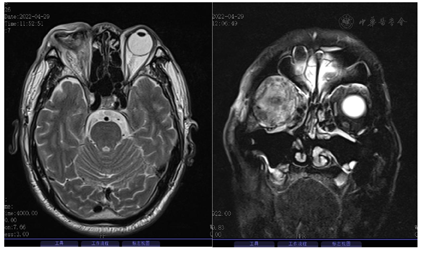

病例1,入院体格检查:体温36.9℃,脉搏110次/min,呼吸26次/min,血压109/88 mmHg(1 mmHg=0.133 kPa),体质量55 kg。神志清楚,精神好。体格检查:左眼未见明显异常;右眼:眼球突出,眼睑红肿明显,内眦上方可见皮肤破溃,表面有血痂,结膜充血,结膜囊内可见大量黄色脓性分泌物及血性分泌物,角膜表面干燥、毛糙,余结构视不入。压痛(-);眼球运动:右眼不能转动,左眼各方向运动未见明显异常。余心肺腹体格检查无特殊。实验室检查:乙肝、丙肝、HIV阴性;痰结核菌涂片阴性,尿常规、甲状腺功能5项、真菌D-葡聚糖检测、梅毒螺旋体血清学、巨细胞病毒DNA测定、呼吸道病原体9项、甲型流感病毒抗原阴性。结核感染T淋巴细胞:阴性。结缔组织疾病阴性。血培养、前列腺脓液培养、眼周分泌物培养:肺炎克雷伯菌(全敏感)。2022年4月2日(术前):右侧眼球3度突出;右侧球后脂肪间隙及右侧眶周软组织所见,考虑炎性假瘤;右侧眼球变形并内密度不均匀增高;鼻中隔偏曲;双侧上颌窦炎并左侧上颌窦囊肿;右侧下鼻甲肥大。2022年4月6日肾输尿管膀胱前列腺,双肾未见明显异常。双侧输尿管未见扩张。膀胱未见明显异常。前列腺增大(考虑:前列腺增生,其他待排)并其内回声不均,建议结合PSA检查。盆腔内低回声区(与前列腺分界不清),结合病史考虑:感染性病灶可能性大,6.3 cm×4.4 cm的低回声(图2)。2022年5月6日(术后)双肺轻度间质性改变,双肺散在炎症,肝右叶低密度,感染性病变可能性大(1.44 cm)前列腺增生,前列腺内低密度灶,考虑感染性病变,脓肿可能。右侧颞叶皮层,左侧小脑半球及左侧放射冠区异常强化结节,考虑脓肿较前水肿范围缩小,结节强化范围及幅度略缩小,请结合临床水肿,右眼球摘除术后改变(图3)。

病例2,入院体格检查:体温36℃,脉搏92次/min,呼吸18次/min,血压96/79 mmHg,体质量75 kg。神志清楚,精神好。体格检查:普通视力检查:右手动/10 cm,左0.4眼压检查(非接触式眼压计);右Tn左11 mmHg裂隙灯检查:右眼:眼睑无水肿、充血、破溃、裂伤,结膜混合充血,角膜内皮可见大量菌栓附着,巩膜无黄染、结节,房闪(+++),虹膜:纹理清,无前粘,后粘,色泽正常,圆,居中,光敏,瞳孔药物性散大,晶状体密度增高,前囊可见渗出膜,玻璃体:积脓。间接眼底镜检查:视不清。裂隙灯检查:左眼:眼睑无水肿、充血、破溃、裂伤,结膜无明显充血,角膜透明,巩膜无黄染、结节,前房深度可,房闪(-),虹膜:纹理清,无前粘,后粘,色泽正常,瞳孔大小3 mm×3 mm,圆,居中,光敏,晶状体密度增高,玻璃体:混浊;间接眼底镜检查:小瞳下网膜未见明确出血及渗出。诊断:右眼EE。余心肺腹体格检查无特殊。实验室检查:乙肝、丙肝、HIV阴性;尿常规、甲功五项、糖化血红蛋白阴性、脑脊液正常、阴性。肿瘤标志物:血清铁蛋白1109 ng/ml;结缔组织疾病阴性;血常规:白细胞18.13×109/L↑,中性粒细胞占比0.848↑,血红蛋白111.00 g/L↓,血小板计数418.00×109/L↑;2022年8月1日门诊红细胞沉降率测定:58.00 mm/h↑;急诊炎症因子组合:C反应蛋白(干化) >90.00 mg/L↑,白细胞介素6 107.5 pg/ml↑,降钙素原全定量1.14 ng/ml↑。血培养、肝脓肿脓液培养:肺炎克雷伯菌(全敏感)。余心肺腹体格检查无特殊。头颅及腹部MRI:(1)脑MRI平扫及增强扫描未见明显异常;(2)右侧眼环增厚,右侧视网膜脱离,右眼玻璃体内异常信号,右侧泪腺及右侧眼眶周围软组织水肿,考虑炎性改变,请结合相关专科检查;(3)肝内多发异常信号,结合病史,考虑多发肝脓肿,肝门区及腹膜多发淋巴结,部分肿大;(4)胆囊炎;(5)肝周少量积液;(6)扫及双侧胸腔少量积液;扫及右肺内异常信号,建议结合胸部CT检查。腹部CTA提示:(1)肝内散在低密度灶,考虑脓肿可能,请结合临床;(2)胆囊炎;副脾;(3)腹膜后散在淋巴结;(4)右侧胸腔积液并部分肺不张,左侧胸膜不均匀性增厚;(5)腹部CTA示左肾双支肾动脉,第三肝门显影。超声造影:肝实质内多发混合性占位灶并其内多发分隔,结合超声造影考虑:肝脓肿并部分液化(图4、图5)。